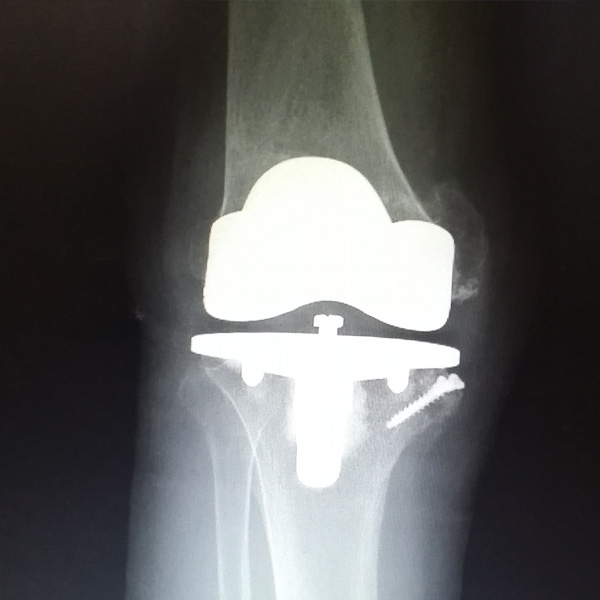

• 膝關節內翻膝關節內翻手術后手術前

膝關節內翻

患者劉某某,女66歲,左側膝關節嚴重內翻(俗稱的“羅圈腿”),疼痛到不能生活自理。經平臺推薦到哈爾濱醫科大學附屬第二醫院骨關節科就診,......

在線咨詢+更多詳情+